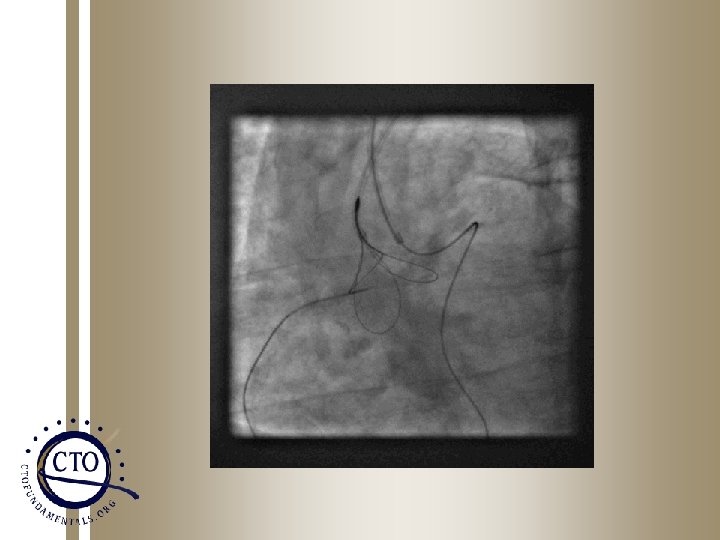

Guideliner assisted Reverse CART